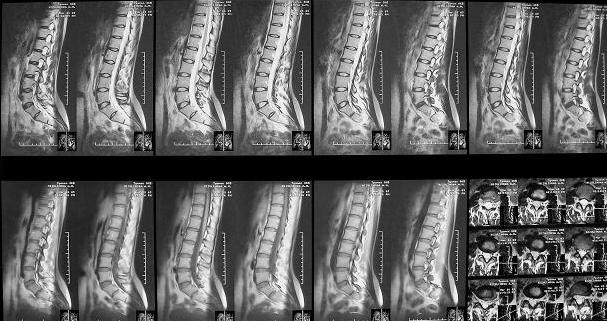

Здравствуйте уважаемые коллеги. Высылаю обещаннное ЯМРТ. Никаких нарушений м\позвонковых дисков, мяггкотканных образований на уровне Th12-S3 не обнаружено.

Пока от проводимого лечения положительной динамики нет.

Видимо прав Алексей Владимирович, и больной пора принимать антидепрессанты и консультироваться у психотерапевта.